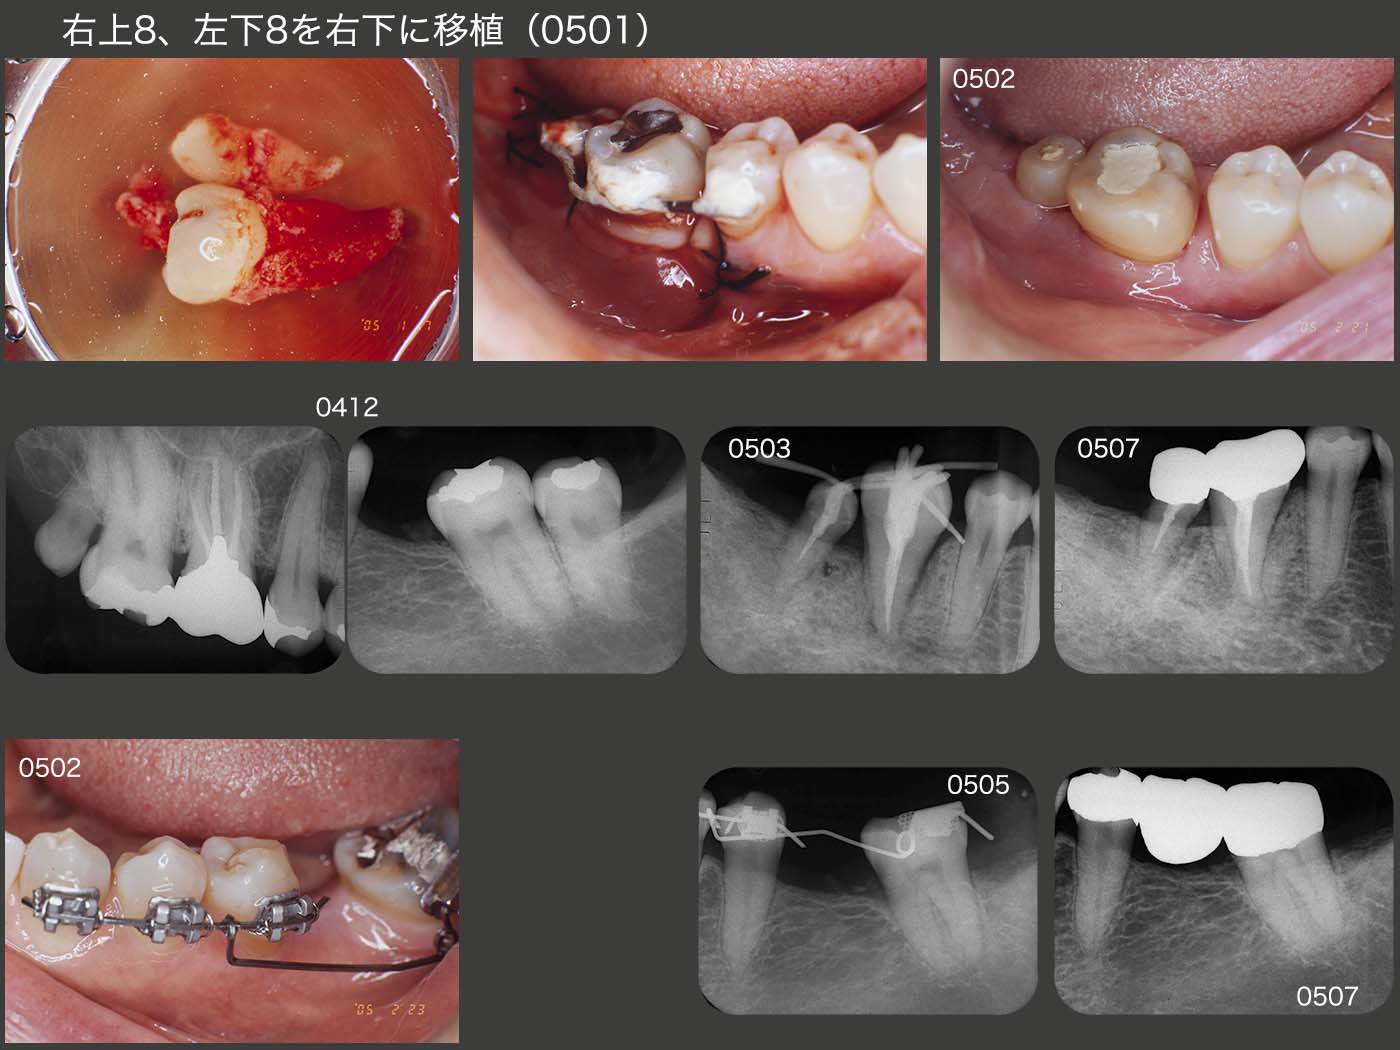

2004年12月初診,52歳の女性.主訴は,1ヵ月半前に右下を他院で抜歯したが,まだ痛みがあり,またあとの治療をどうしたらよいか悩んでいるとのこと.以前左下6を抜去後,放置したために左下7が近心傾斜していることから,左下8をドナー歯として右下に移植し,左下7をアップライトすれば,全体のバランスがとれることを説明し,同意を得た.また右上8も非機能歯であることから,この歯も一緒に移植することにした.